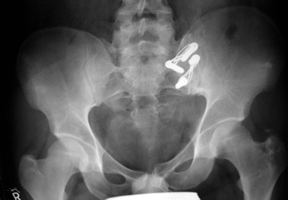

Vordere und hintere Beckenringfraktur bei Polytrauma. Hier ist die Stabilisierung mit Fixateur allein nicht stabil genug. In einem solchen Fall sollte zuerst die hintere Fraktur mit Platte, Schrauben oder wie in diesem Fall mit mit einer Drahtgurtung stabilisiert werden. Danach wird der Patient in Rückenlage gebracht und der Beckenring vorne mit einem Fixateur befestigt. Belastung ist meist nach 4-5 Wochen möglich.